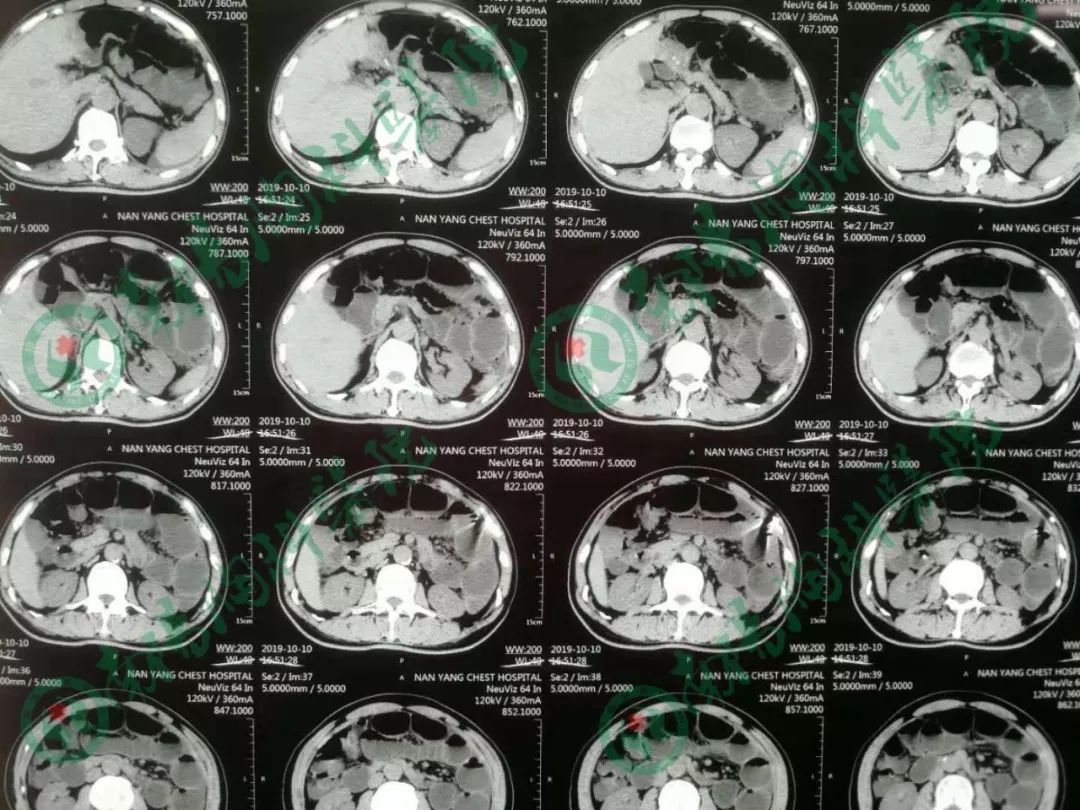

患者经过立位DR和CT检查均提示肠管高度扩张,多发阶梯状液平,病情非常棘手。

告知急诊手术,术中探查见小肠高度扩张,末段回肠扭转粘连于盆底骶前,放射性肠炎改变,呈冻结状,部分肠管受压坏死,行末段冻结扭转回肠切除术,小肠造瘘术,术后病人生命体征平稳,安返ICU。